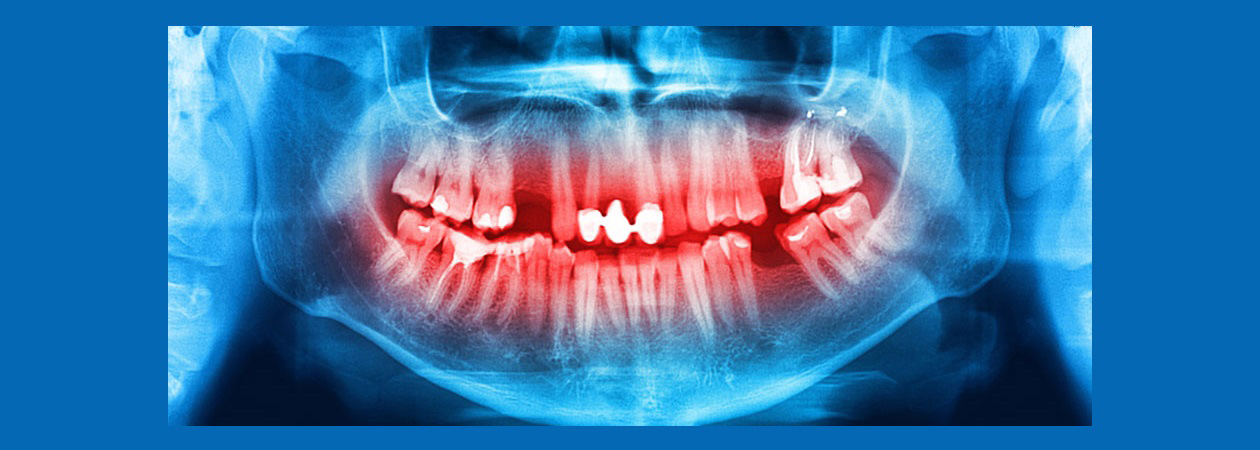

آسیبهای فک و صورت

پاتولوژی

کیست

تومور

جراحی داخل دهانی

دندان نهفته